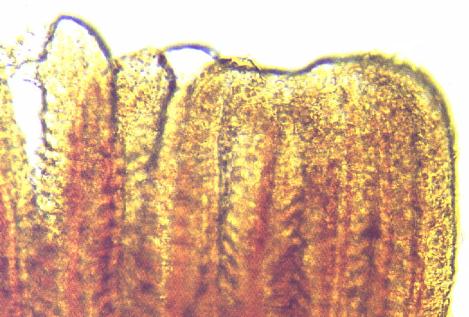

鰓に寄生した場合は、上皮細胞が侵蝕され、粘液が大量に分泌されて呼吸機能が低下し、斃死しやすい。

イクチオボドは、寄生虫としては非常に小さい部類に入るので、顕微鏡でも見落とすことが多い。ほんの少し鰓を切り取って、5分間ぐらいの時間を置いてから観察すると、鰓に付着していた虫が、時間の経過につれて離れて動くので、見えやすくなる。スライドグラスにとり、200~400倍の顕微鏡で確認すると、形態は卵形で、腹側が多少湾曲し、口の部分に四本の鞭毛があり、そのうち二本は長い。この鞭毛で運動し、くるくると非常に早く回転する。